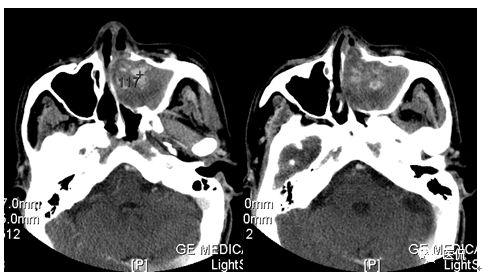

增强动脉期

CT平扫及增强示:左侧上颌窦及鼻腔可见软组织密度影,呈膨胀性生长,周围骨质压迫性吸收破坏,累及左眶,病灶密度不均匀,周边区可见点状钙化,增动脉期轻度强化,局部见小灶性稍高密度区,静脉期病灶内见不均匀明显强化,CT值最高达117HU,延迟期强化范围有所增大。

影像学表现呈软组织密度,多不均匀,表现为高低混杂密度,病变窦腔内息肉、血肿、坏死、感染共存,是病灶密度不均匀的主要原因,息肉反复出血、血管机化亦为其成因之一。病灶内钙化,可为团块状或小片状,可能为病变组织坏死后钙质沉着所致。由于病变组织内有大量炎性细胞浸润和丰富的毛细血管,增强后常有强化。有文献报道病灶增强中心区强化不明显,外周呈轻度强化,推测病灶内虽然血管丰富,但中心区容易出现血流动力学障碍,血管内常有血栓形成,中心区易发生出血坏死,另外,可能与增强扫描延迟时间选择不当有关。

本例病灶较大,周围骨质可见吸收破坏,并累及眼眶,病灶内少量钙化,增强扫描具有一定特征性,表现为动脉期轻度强化,局部见小灶性稍高密度区,静脉期病灶局部呈明显强化,CT值最高达117HU,延迟期强化范围有所增大,呈延迟渐进性强化的特点,推测为病灶内出血所致。